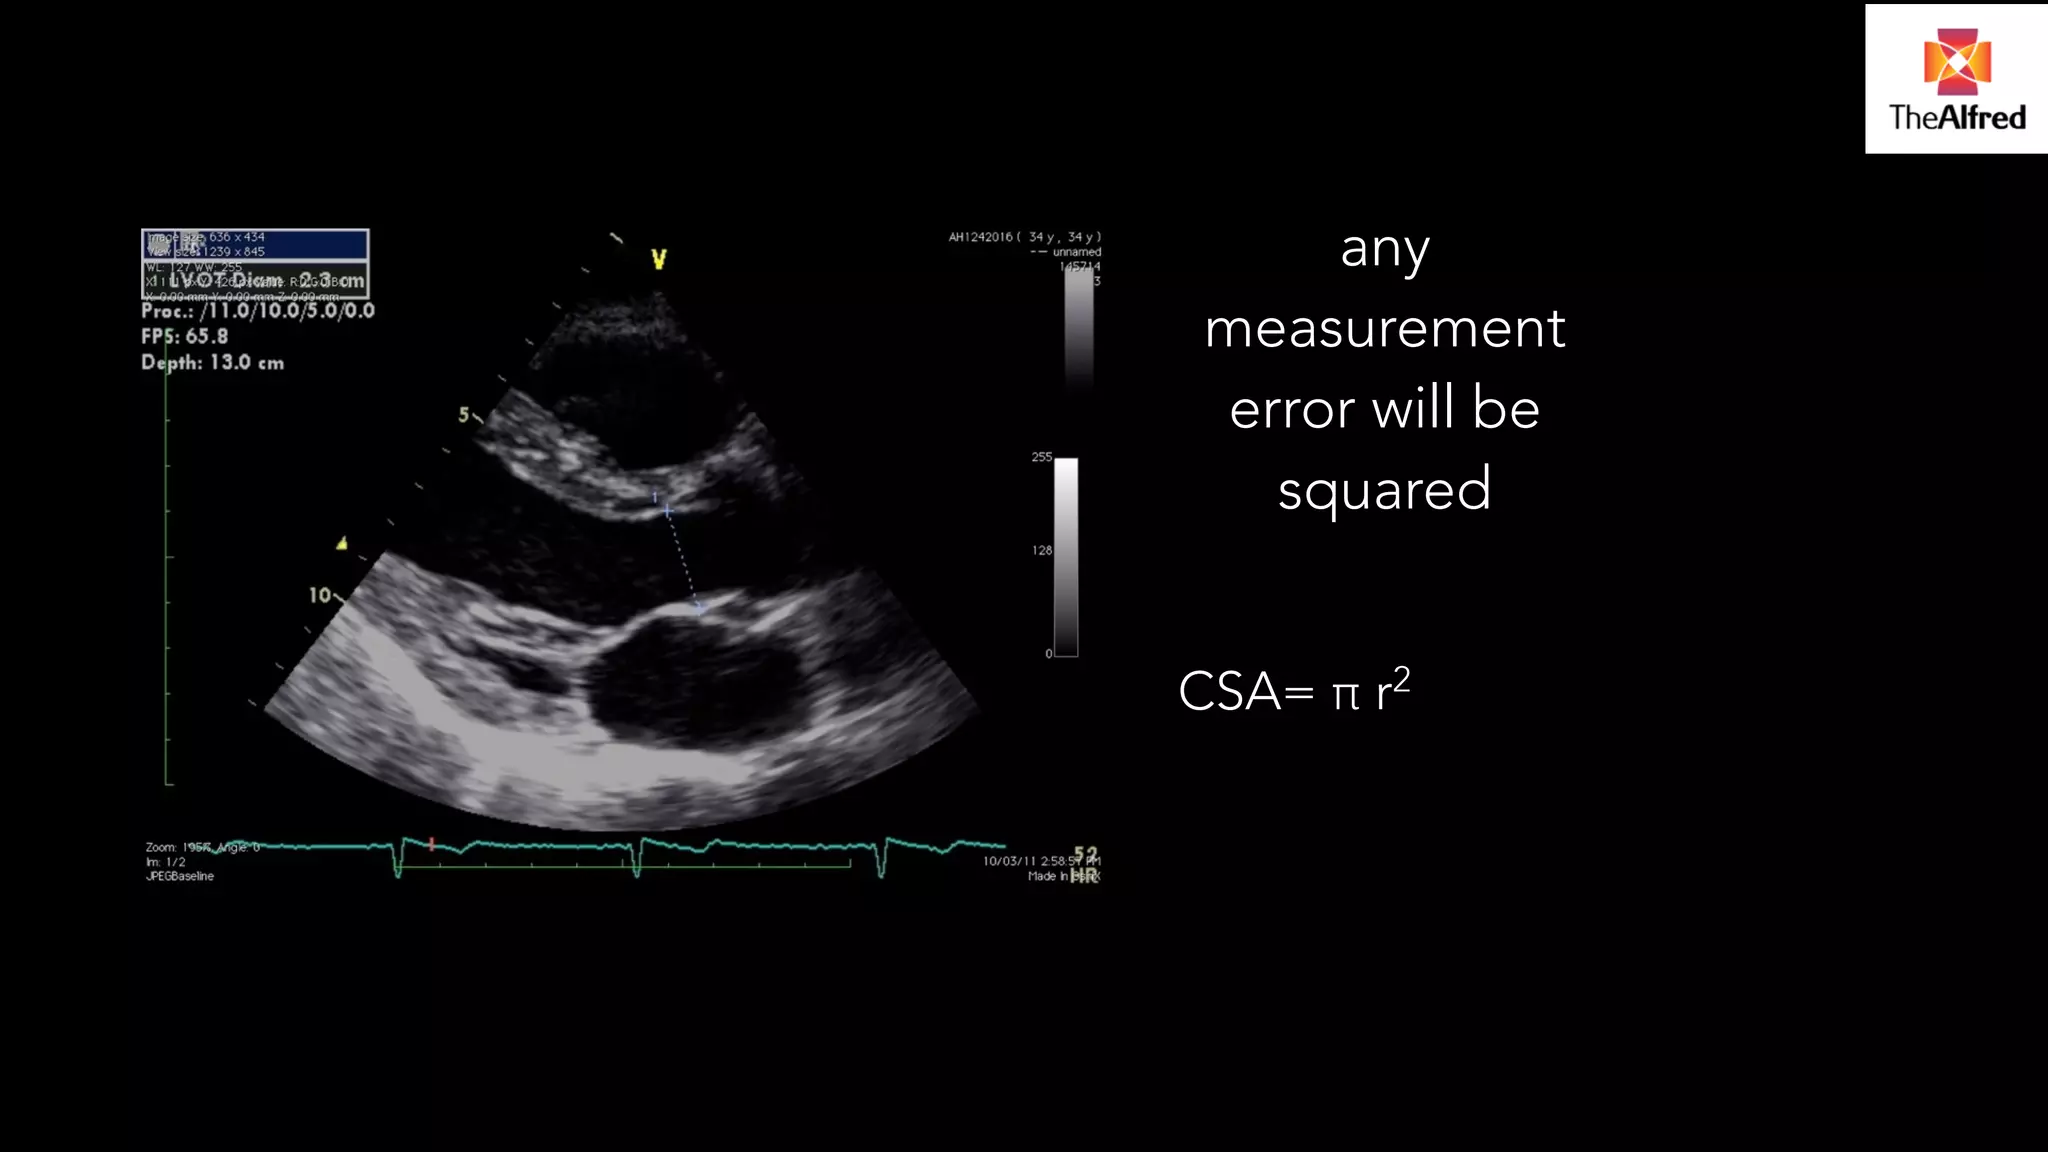

MATHS… Volume =CSAX height (distance) ! Stroke volume= π r2 X VTI ! Cardiac output= SV x heart rate

• 11.

any measurement errorwill be squared ! CSA= π r2

Stroke volume= π r2 X

VTI

!

Cardiac output= SV x

heart rate

any

measurement

error will be

squared

CSA= π r2